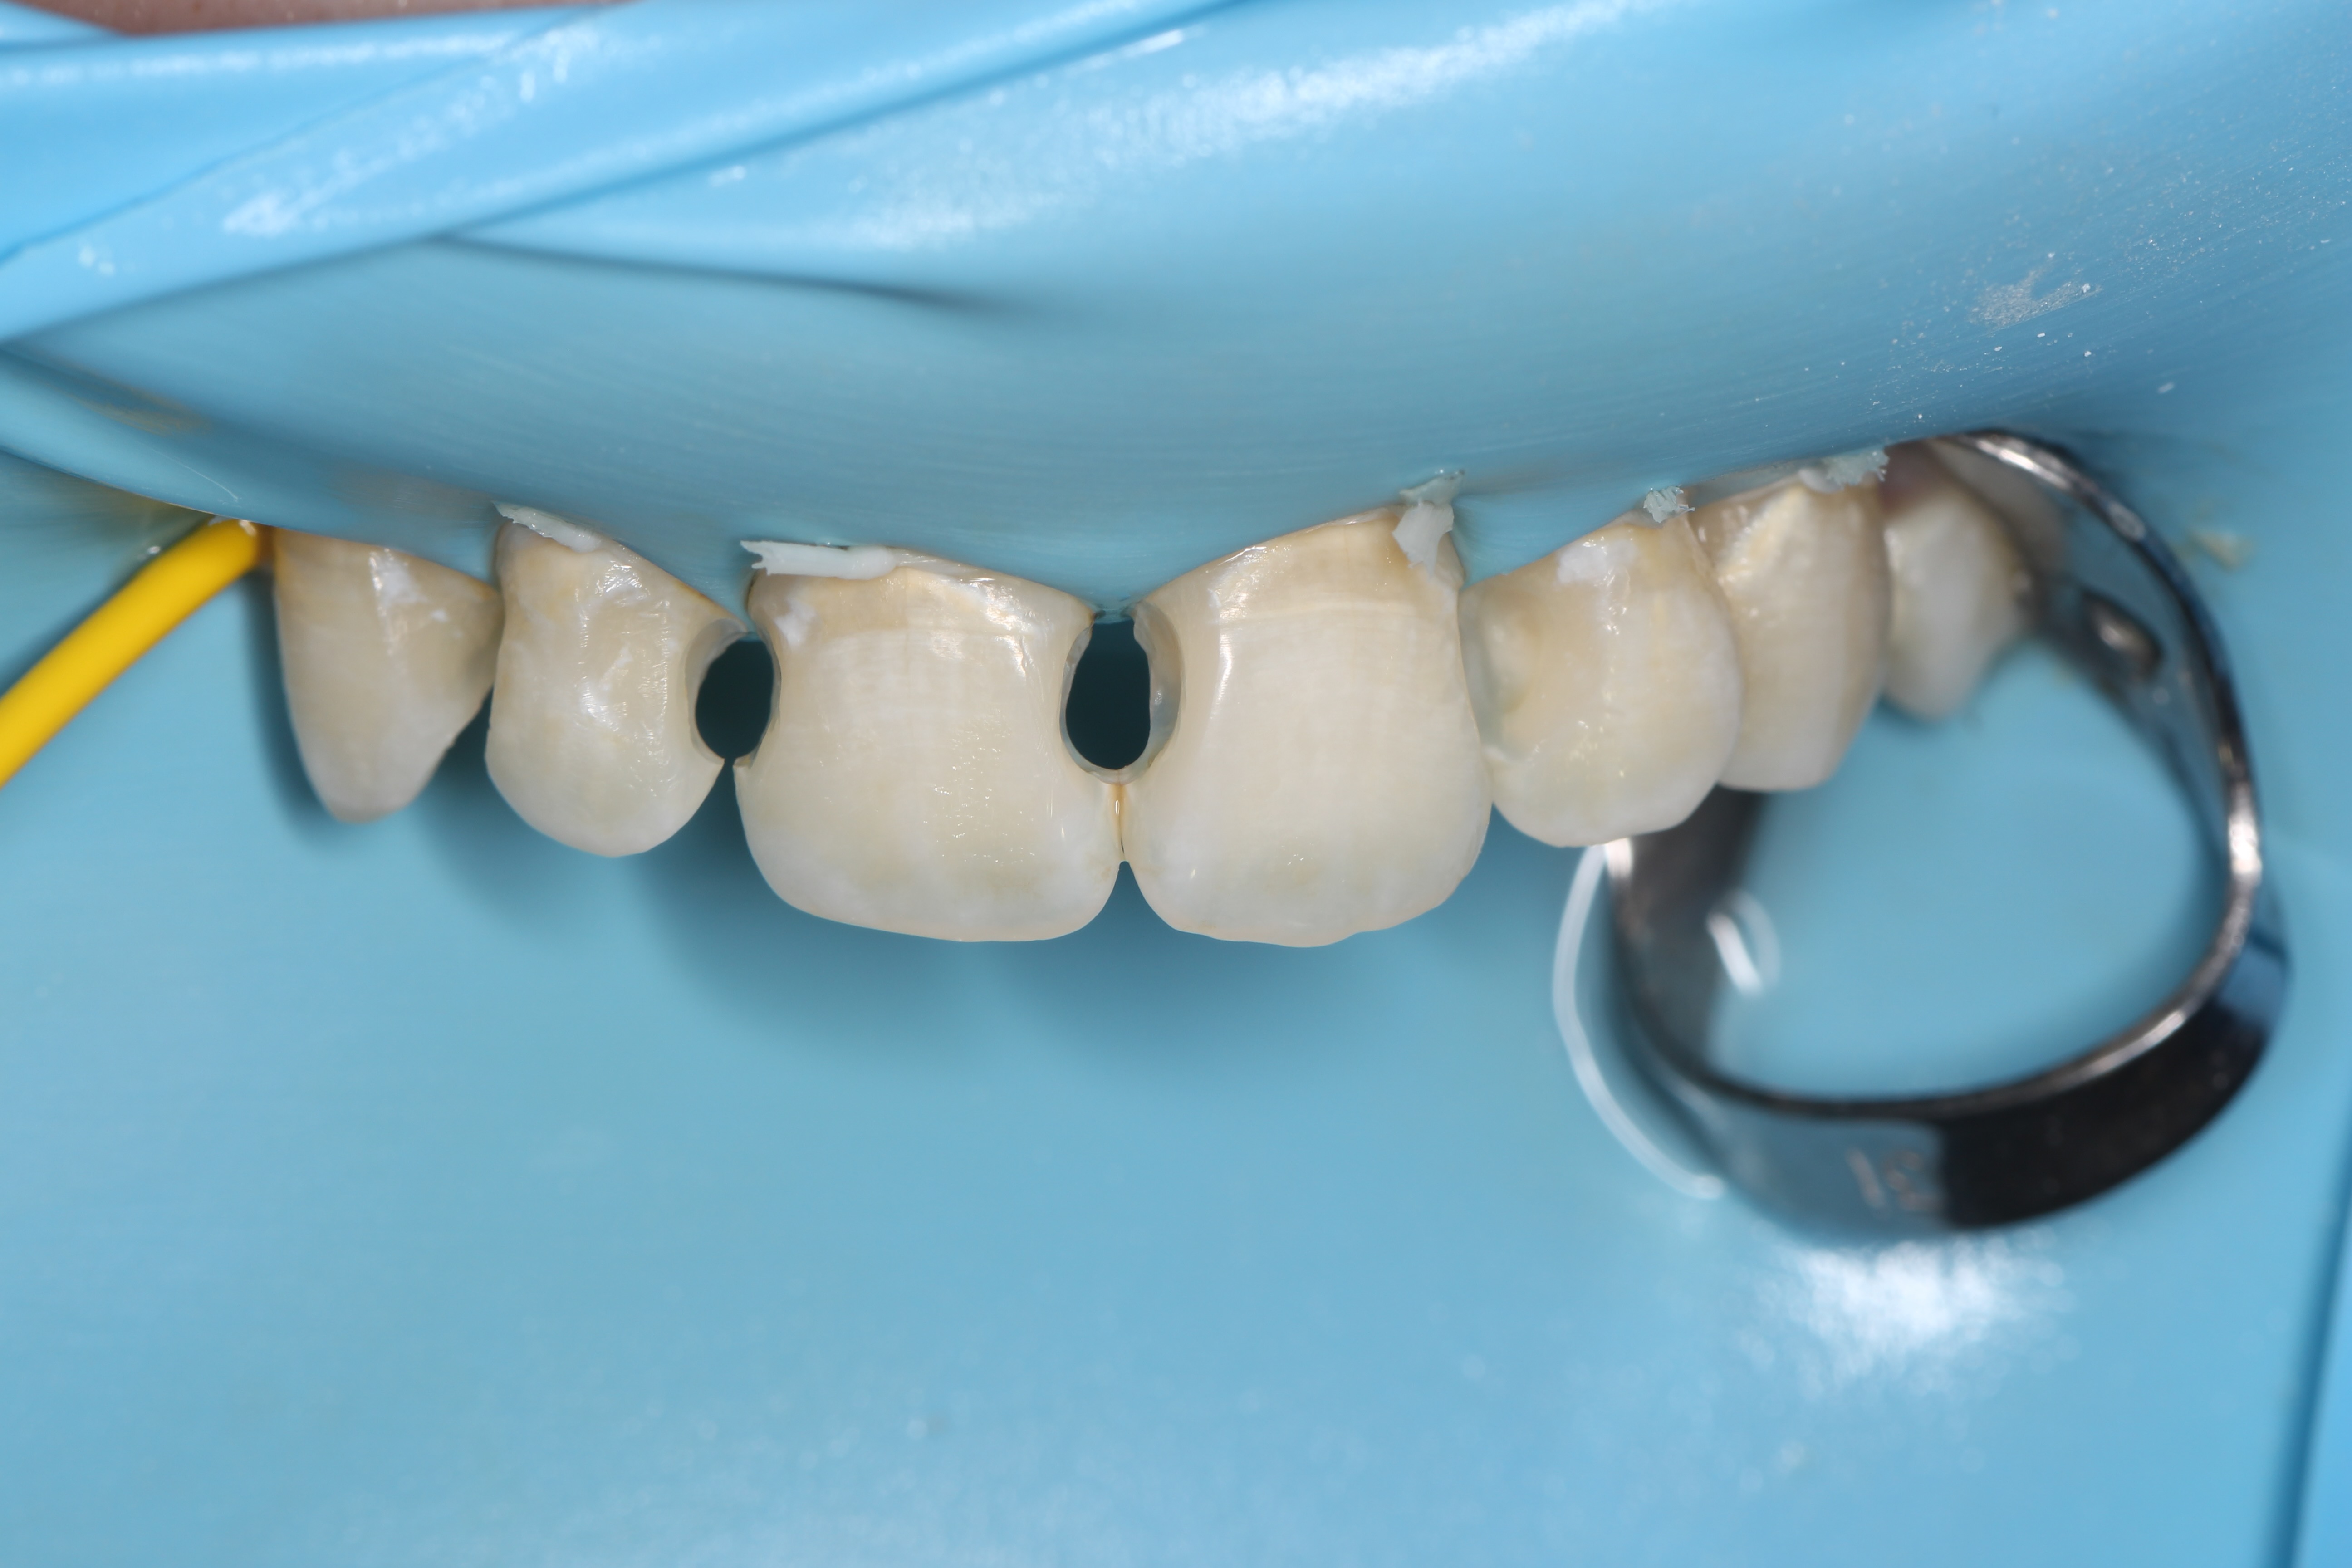

Anterior ceramic crowns and smile design by Mr Stefano Del Monte

From this course, I learned the whole workflow involving designing crowns for an aesthetic case. I learned how to work alongside the lab to create digital smile wax-ups, how to manage patient expectations and prepare teeth quickly and effectively for anterior crowns and veneers.play your timeline of professional development